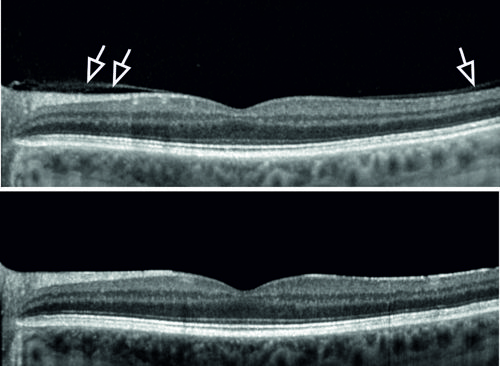

OCT imaging shows vitreous attachment preoperatively (top) and development of PVD at 3 months after cataract surgery (bottom).

Determining vitreous and retina status preoperatively will help surgeons identify patients at risk for RRD after cataract surgery. Vitreous attachment is easily identified using optical coherence tomography (OCT), and Dr Zinkernagel mentioned that a project underway in his department aims to develop a deep learning-based screening system for automated detection of peripheral retinal breaks and detachments on fundus photography images.6